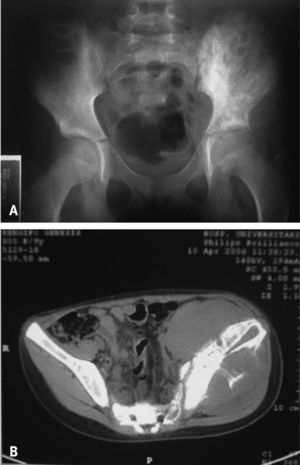

La radiografía de pelvis mostró lesiones líticas múltiples y esclerosis en el hueso ilíaco izquierdo (fig. 1 A). La gammagrafía ósea reveló aumento de la captación en la región sacroilíaca izquierda, y la tomografía computarizada, una tumoración hipodensa que ocupaba el hemisacro izquierdo, y causaba periostitis, apoptosis y deformidad del hueso (fig. 1 B). La biopsia de la médula ósea mostró hipercelularidad y alteraciones en la morfología celular compatible con leucemia mieloide aguda (LMA). El diagnóstico definitivo de leucemia se realizó 2 meses después del inicio de las manifestaciones clínicas.

Los casos que comunicamos coinciden con la literatura en la forma de presentación clínica, con patrón de curso migratorio predominante, distribución oligoarticular y afección predominante de grandes articulaciones. Uno de nuestros niños tuvo una presentación infrecuente por la afección del sacro y el desarrollo de una tumoración de partes blandas invasiva y osteolítica (figs. 1A y B). Dos de los 3 casos tuvieron enfermedad febril, manifestación sistémica más frecuentemente observada en este tipo de pacientes3,7 y común también en pacientes con ciertas formas de AIJ. La niña fue inicialmente clasificada como una espondiloartropatía juvenil, por el dolor sacroilíaco debido a la tumoración de partes blandas a ese nivel. No hemos encontrado informes en la literatura de casos de leucemia aguda confundida con espondiloartritis.